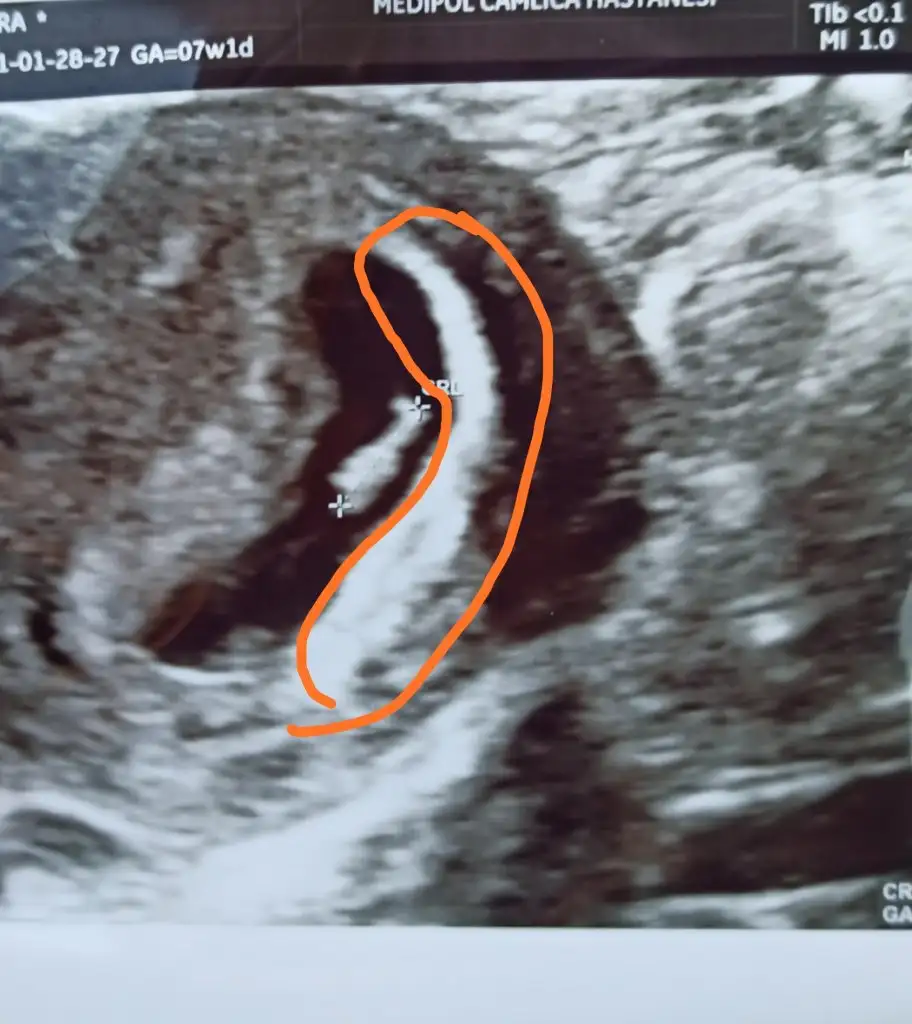

Plesanta çizdiğim yerdeki beyazlık mı oluyor acaba

Kızlar birde nub teorisi mi var:emir_bebek: Bilenler bize de bir tahmin de bulunabilir mi:) 11+3 idik bir hafta önden gidiyormuşEki Görüntüle 2789737

Canım nub pek belli olmuyor gördüğüm o ise kız gibi 30 derece altında :)) yaa inşallah 12.hafta bende böyle bir şey görürüm bin kere maşallah canım. 💙